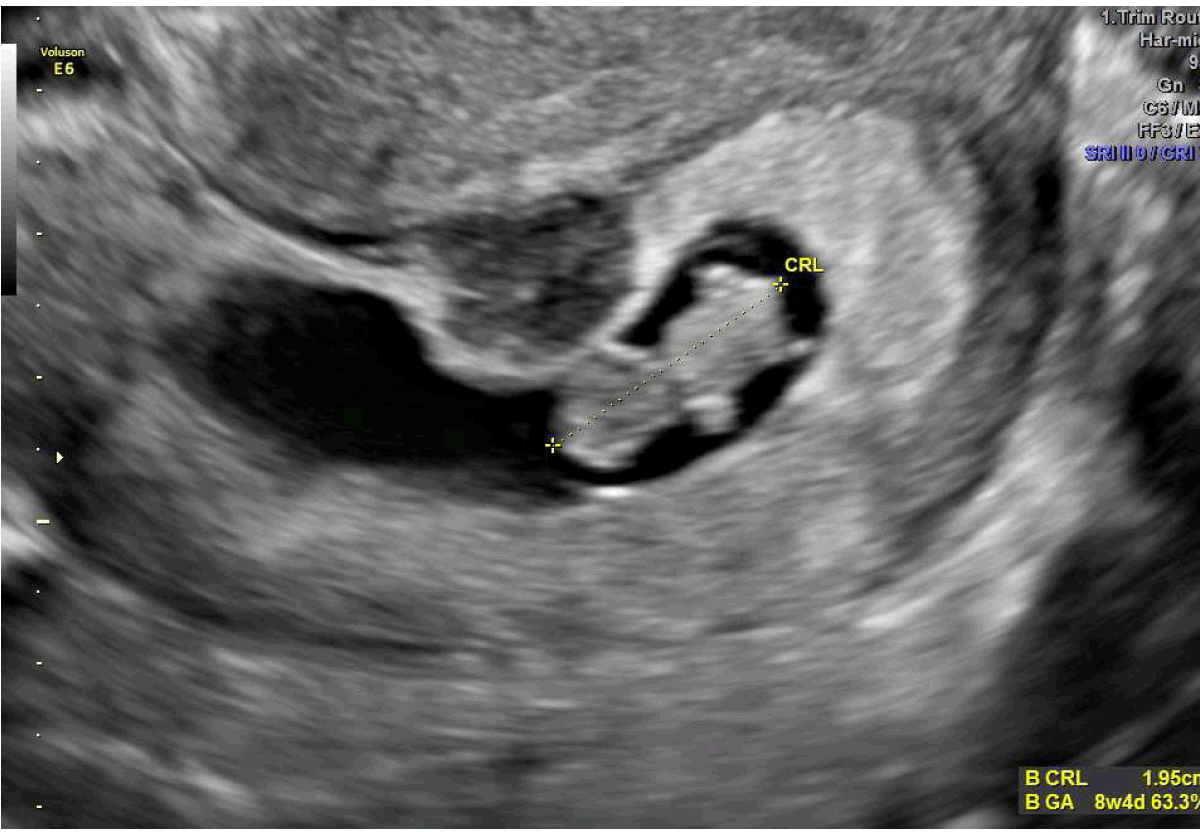

A 29-year-old female presented to the emergency department at our hospital with complaints of mild abdominal pain associated with nausea. Physical examination findings were normal with stable vital signs and a slightly elevated white blood cell count of 14x103 cells/mm3. A transvaginal ultrasound scan revealed di-amniotic di-chorionic twin intrauterine pregnancy at 6 weeks and 2 days gestation as well as normal sized ovaries with arterial and venous flow to both ovaries. The patient reported no use of assisted reproductive techniques in conception. Of significance, she also reported spontaneous conception of di-amniotic di-chorionic twins, delivered vaginally at 35 weeks, 3 years prior to presentation to the emergency department. Her history was only notable for breast augmentation after her twin delivery, multiple urinary tract infections, former 14-pack per year smoker and the use of Depo-Provera for 12 years. After satisfactory workup in the emergency department and with consultation from the obstetrics and gynecology team, the patient was discharged to follow-up as an outpatient for a repeat ultrasound. At eighth week and four days she presented to the office, where a repeat transvaginal ultrasound scan revealed twin gestation with an ectopic pregnancy situated in the right tube, close to the right ovary (Figure 1) (Figure 2) (Figure 3). Given the patient' stable clinical status upon presentation, she was scheduled for laparoscopic surgery the following morning. A few hours upon leaving the office, the patient presented to our emergency department complaining of severe lower abdominal pain. An acute abdomen was diagnosed on physical examination with stable vital signs, white blood cell count of 16x103 cells/mm3, hemoglobin 11 g/dL, hematocrit 34%. A diagnosis of a ruptured ectopic was made clinically mainly based on the acute abdomen. As a result, the patient was taken for an emergent laparoscopy. Upon entry into the abdomen, the right tubal pregnancy with partial implantation on the broad ligament had ruptured with significant hemoperitoneum. A fimbriectomy was carried out without complications. The patient tolerated the procedure well and was discharged the following day in stable condition. | ||||||